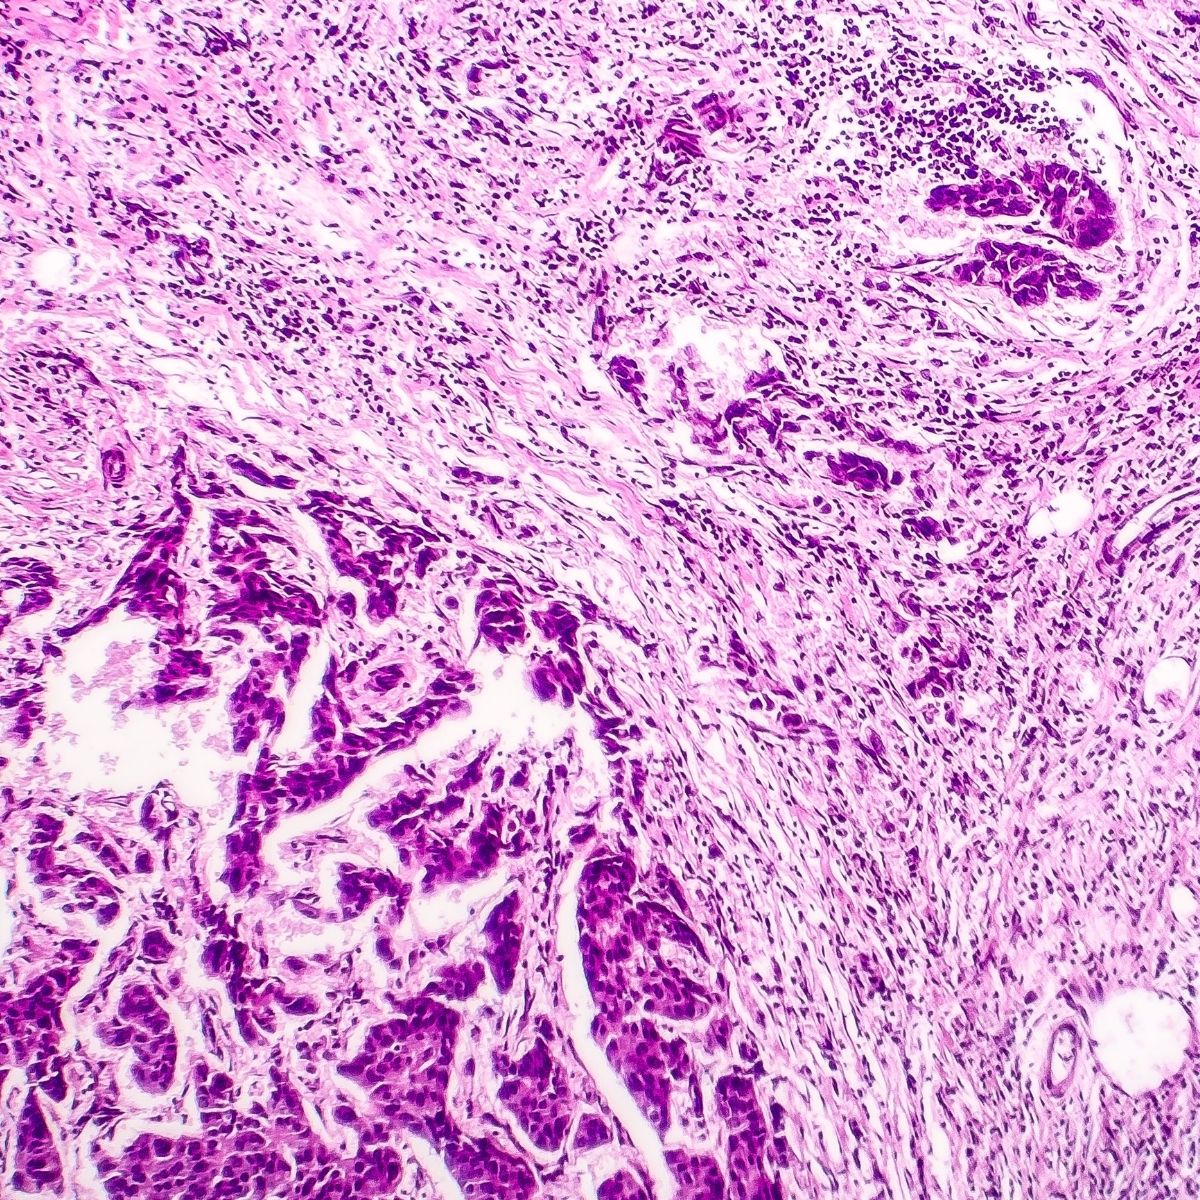

Diagnosis is done on the basis of symptoms narrated by the patient and the examination carried out by the doctor. A history of cancer helps in confirmation of the metastasis. Head to toe examination is carried out. Biopsy for testing of bone tissues is the diagnostic test. Certain other investigations like routine blood test, X-rays, CT scans, MRIs, PET are other test indicated. Other routine investigations like routine blood test, blood calcium levels, urine test etc are also done.